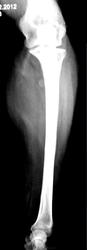

Пациентка направлена на рентгенографию костей предплечья.

Мягкотканное муфтообразное образование в/3 предплечья, с костями предплечья не связанное. Вызывает сомнение плотноинтенсивное округлое включение в мягких тканях по луче-ладонной поверхности на уровне верхней трети лучевой кости.

Мое мнение, судя по распространению мягкотканного образования от суставной капсулы локтевого сустава - синовиома. Относительно плотноинтенсивного включения ответить затрудняюсь.

У пациентки хорошо видимое опухолевидной образование, безболезненное. Пациентка отмечает, что данное образование заметила около 4- лет тому назад, и которое в последние два года значительно увеличилось в размерах. Жалобы у пациентки чисто косметического характера.

Скорее всего липома, есть просветление... Нельзя исключать липосаркому, раз быстрый рост...